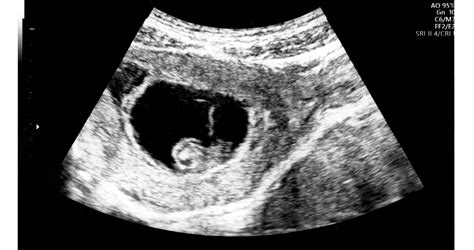

A 6. hét körül érdemes lehet felkeresni a nőgyógyászt, különösen, ha korábbi vetélésed volt, vagy ha vérzést tapasztalsz. Az első nőgyógyászati vizsgálat során általában hüvelyi ultrahangot végeznek, amelyen már látható a petezsák és a pulzáló szív. Ez az élő terhesség első vizuális bizonyítéka.